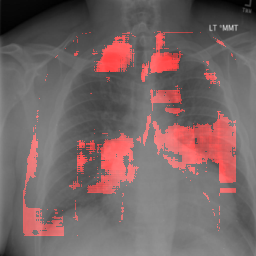

4.2.1 Cardiomegaly Localization

The localization of abnormalities in cardiomegaly examples are shown in Fig. 7. Here, of the image area is shown which has the highest sensitivity. It can be observed from the figures that the network is indeed most sensitive to the region where the heart is larger than a normal heart. We have performed this experiment on cardiomegaly and normal images and found this localization to be consistent for most examples. There is not much functional difference between a normal and cardiomegaly example other than the fact that the heart in cardiomegaly is larger than a normal heart. Given the fact that the normal images could also have various size of heart depending on the age or physical attributes of a patient, we found this level of localization sensitivity to be remarkable. Also interesting is the fact that the standard rule based features like CTR and CTAR take into account the relative size of heart and lung to determine if there is cardiomegaly present or not. In the DCN localization experiment, we see counter-intuitively that most of the signals contributing to the softmax score are coming from the heart only. This means that there are characteristic features in the shape of the heart and its surrounding regions that alone is sufficient to detect cardiomegaly. The lung and its relative size are probably less important features when trying to detect cardiomegaly. This observation is counterintuitive and needs to be explored further in future work.

8 Additional Examples of Localization

In this section we show more examples of localization. Few localization samples are shown in Fig. 11. It can be observed that, in the CXRs with Cardiomegaly (Fig. 11(a) and (b)) a fine localization around the heart is observed. In the normal CXRs (Fig. 11(c) and (d)) such localization is not observed. Rather the lowest probabilities are spread out in the CXR image. It is interesting to note that, the localization algorithm gets low probability where the heart is enlarged during cardiomegaly, but the proportion is small compared to the localization in other areas of normal CXRs. In order to observe the performance of the heat map we computed histograms of heat maps of each of the 100 CXRs in the test set for Cardiomegaly detection and average histograms are shown in Fig. 11(e) and (f) for CXRs with Cardiomegaly and normal CXRs, respectively. It is to be noted that, the histograms include both success and failure cases. It can be observed that, for CXRs with Cardiomegaly the classifier is highly sensitive toward Cardiomegaly detection even under occlusion. This indicates that, the classifier primarily looks for local features in a CXR instead of some feature that is spread out in the entire CXR. However, the classifier is not sensitive toward normal CXRs under occlusion. Rather, the probabilities are spread out in the probability spectrum. After that, we analyzed the failure cases where the classifier is unable to classify the image correctly. Two such examples of failure cases are shown in Fig. 12. The localized CXR shown in Fig. 12(a) contains Cardiomegaly whereas the classifier detects it as normal. However, the localization shows that it localizes around heart quite well despite the in accurate classification. On the other hand, Fig. 12(b) shows an example of normal image which has been classified as Cardiomegaly by the classifier. There is stronger localization around the hear that that is observed for normal images as in Fig. 11(c) and (d), however, like those images the localization is spread out.